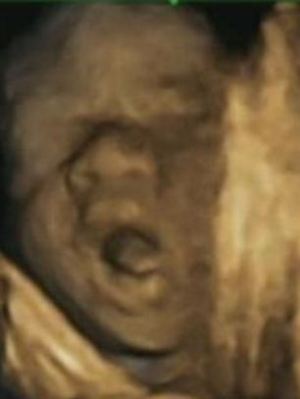

Ψυχολόγοι εντόπισαν ότι τα έμβρυα έχουν τη δυνατότητα, όσο αναπτύσσονται και στα τελευταία στάδια της εγκυμοσύνης, να προβλέπουν και όχι απλά να αντιδρούν στις κινήσεις των χεριών τους προς το στόμα τους. Παράδειγμα τέτοιας πρόβλεψης αποτελεί το άνοιγμα του στόματος πριν την είσοδο του δαχτύλου.

Τα ευρήματα αυτά προέκυψαν από τη μελέτη «υπερηχογραφημάτων 4D», δηλαδή τρισδιάστατων υπερηχογραφημάτων που μπορούν να ιδωθούν σε πραγματικό χρόνο, για την απεικόνιση 8 κοριτσιών και 7 αγοριών μεταξύ της 24ης και 36ης εβδομάδας κύησης.